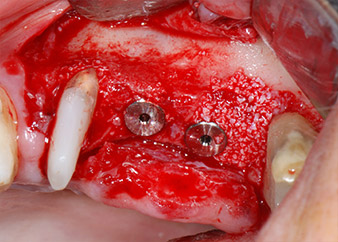

Low speed insertion of implant 26

Fig. 11: Low speed insertion of implant 26 with a torque limitation of 35 Ncm.

ready for the cover screws

Fig. 12: Both implants in place and ready for the cover screws.

The implants (Restore, Keystone Dental, diameter 3,75 mm, length 8.0 mm) were placed with the implant motor

(Figs. 11 and 12).